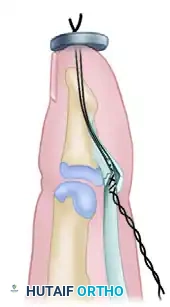

Figure 3: The completed Wagner technique of profundus advancement, showing the tendon secured into the distal phalanx and tied over a dorsal pull-out button.